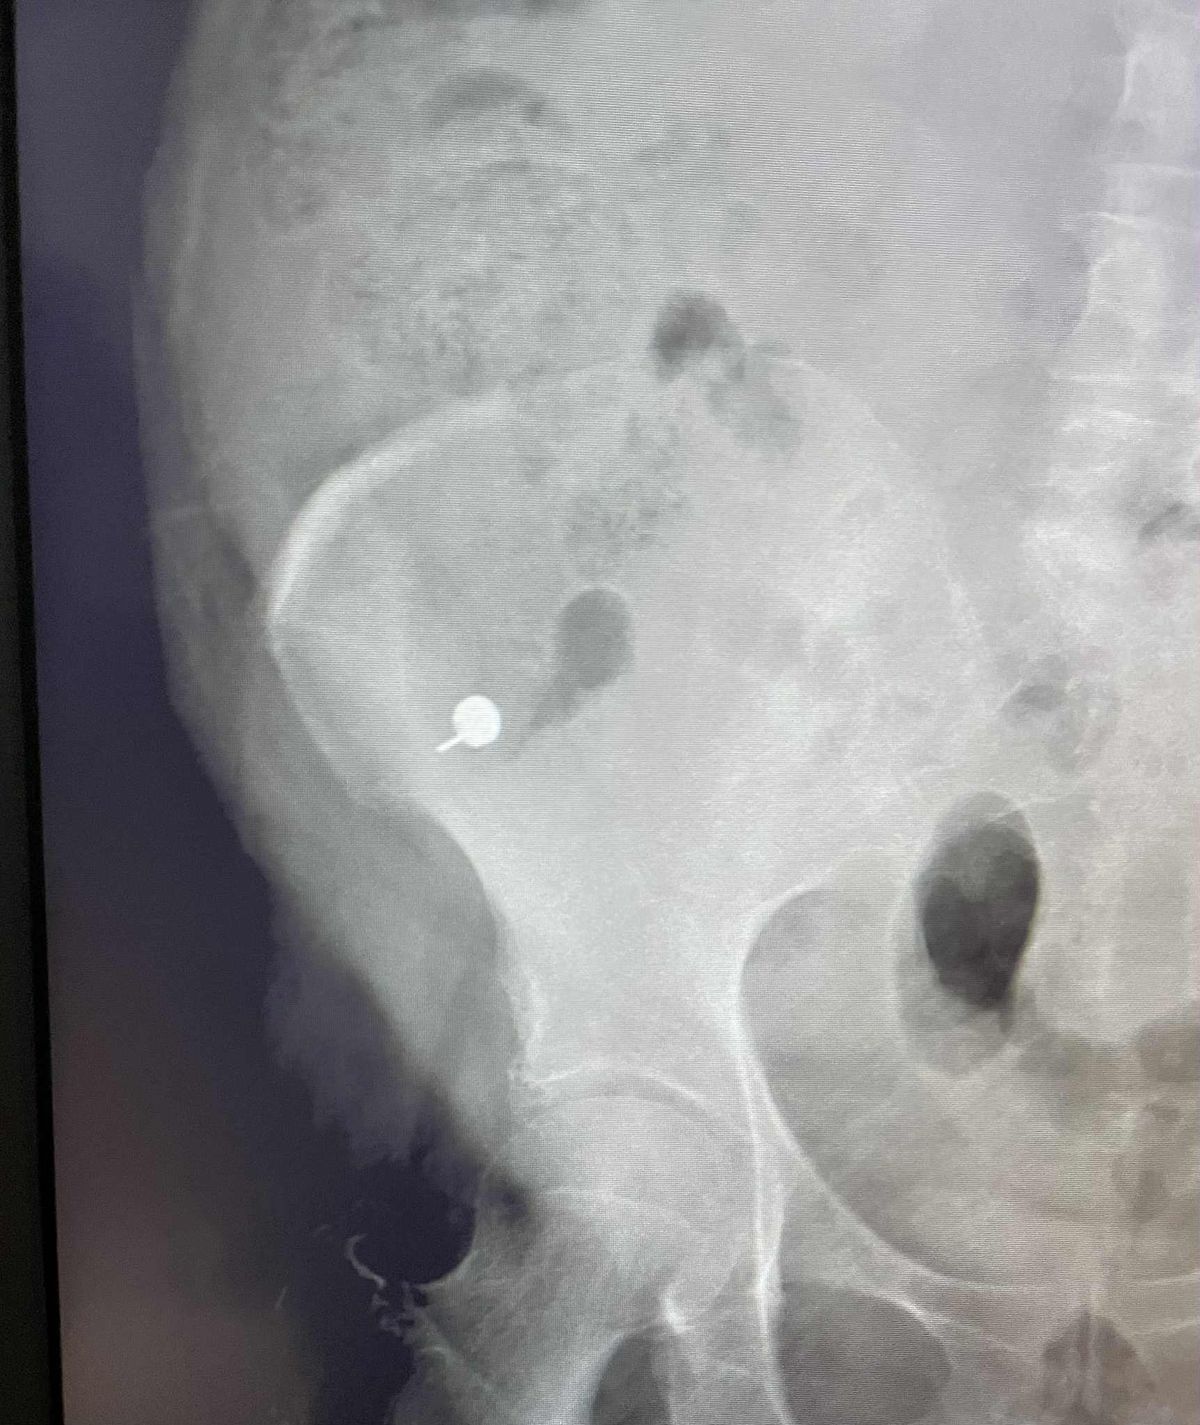

A röntgenfelvétel igazolta, hogy az ékszer valóban a bélrendszerembe került. Egy kicsit nevettek rajtam, de az orvosom nyugodt hangon közölte, hogy ne aggódjak, a fülbevaló valószínűleg természetes úton távozik majd. Azt is elmagyarázta, hogy a tárgy már a vastagbélben van, ahol jóval kisebb az esélye annak, hogy problémát okozzon

- sóhajtott Andrea és megosztotta velünk a röntgenfelvételt.